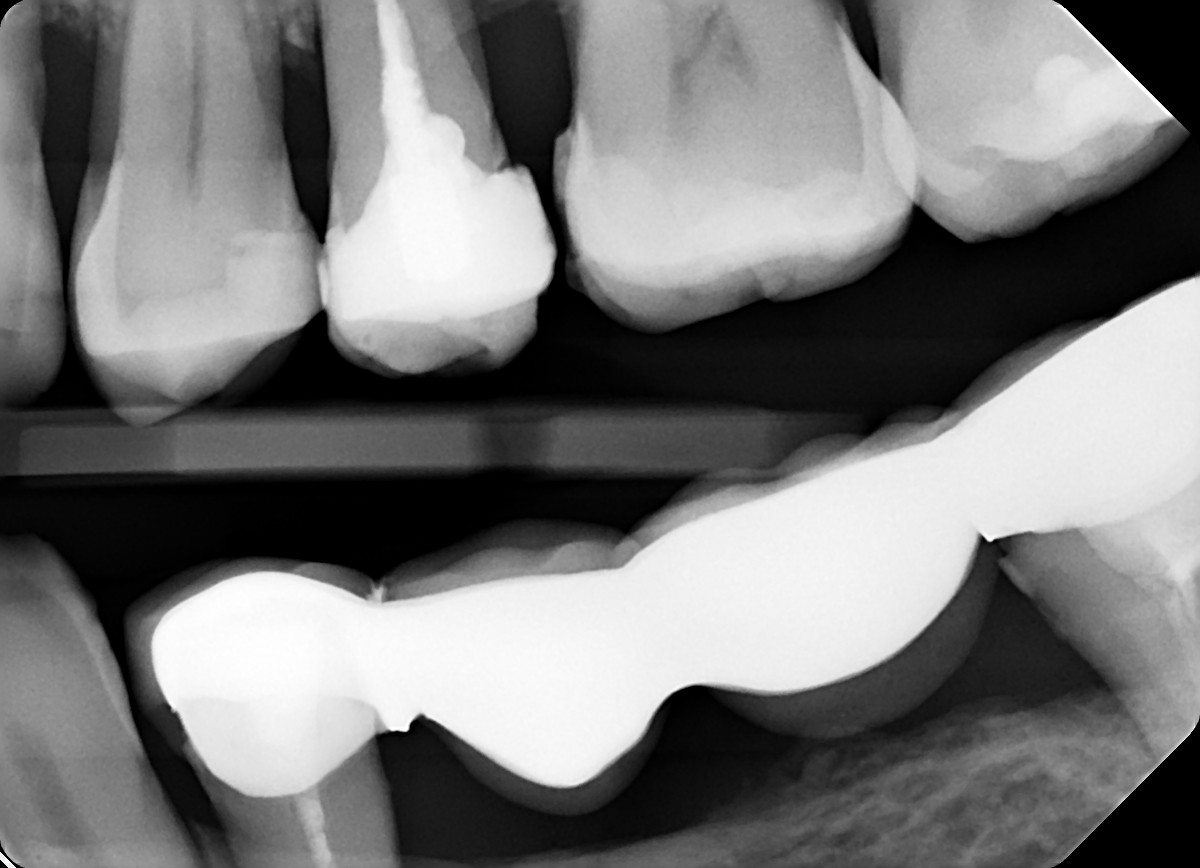

2. What option can be selected for the X ray bellow?